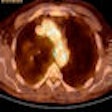

CT, MRI look at different etiologies for myocardial fat